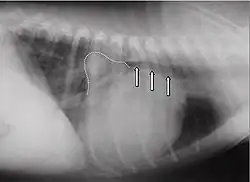

Les autres méthodes d'investigation ne sont nécessaires que pour l'analyse de complications éventuelles, ou dans le cadre du bilan pré-opératoire. C'est ainsi que l'électrocardiogramme, ou éventuellement l’électrocardiogramme à longue durée (Holter) peuvent aider au diagnostic de perturbations du rythme cardiaque, ou montrer des anomalies pouvant évoquer une cause à la fuite mitrale (infarctus du myocarde par exemple). l'électrocardiogramme peut cependant être strictement normal, même en cas de fuite importante.

La radiographie du thorax ne montre pas de signe spécifique : éventuellement augmentation de la taille du cœur et surcharge vasculaire suivant le retentissement de la fuite mitrale.

Les signes les plus fréquents d'une capacité cardiaque diminuée sont : la diminution des performances, la toux, les troubles nocturnes et la dyspnée. À l'auscultation, on[Qui ?] peut entendre dans la plupart des cas des bruits cardiaques holosystoliques d'intensité constante, de force des plus variables (degrés 1 à 6). Le bruit maximum de la valve mitrale (punctum maximum) est chez le chien dans le 5e espace intercostal, au niveau de la pointe du cœur. À la radio, un cœur dilaté peut être constaté. L'atrium gauche peut alors revêtir la forme d'un triangle (« triangle mitral ») décalé en direction caudo-dorsale. L'angle usuel entre les bronches et la colonne vertébrale peut disparaître en un trajet parallèle, et même l'atrium peut comprimer les bronches et l'irritation mécanique augmente alors les symptômes de toux. Dans les cas avancés, un œdème pulmonaire est diagnostiqué. L'électrocardiogramme est en général peu spécifique, il y a en partie des suggestions d'atrium dilaté (onde P allongée, au-delà de 0,04 s) ou d'un ventricule dilaté (complexe QRS plus long que 0,06 s). En outre, il peut y avoir des extrasystoles auriculaires ou ventriculaires, parfois une fibrillation auriculaire. Ce symptôme est fréquent chez les chiens avec une insuffisance mitrale fonctionnelle due à une cardiomyopathie dilatative. À l'échocardiographie Doppler, il est facile de reconnaître une insuffisance mitrale. Les autres conséquences qui surviennent sont : un élargissement du ventricule en raison de la surcharge en volume, souvent une hypercontractibilité en raison de mécanismes de compensation, et une oreillette substantiellement agrandie.